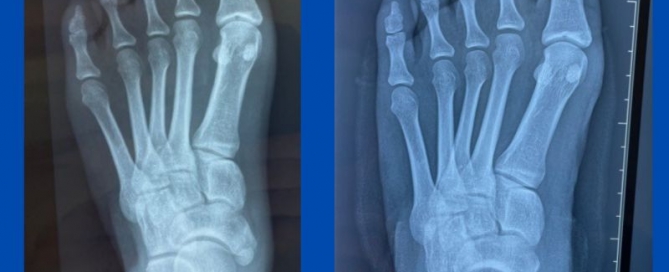

Biomechanics of a pathology (bunions and pes planus)

Blog's main page This is a great example of how poor biomechanics impacts foot pathology. This is a case of juvenile bunions with flat feet that has recently been presented [...]